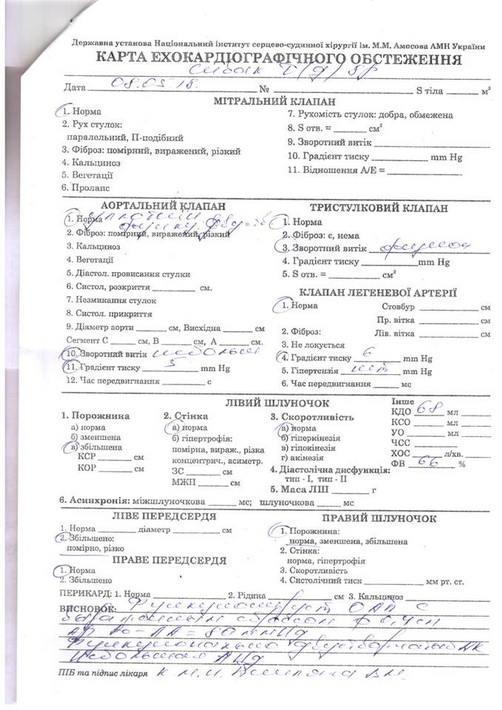

Останнім часом дитина почала швидко втомлюватись, скаржитись на погане самопочуття. Нещодавно при обстеженні було виявлено, що вона має дві вроджені вади серця, про які батьки раніше навіть не здогадувались: відкрита артеріальна протока та двостулковий аортальний клапан.

“Нещодавно ми були на консультації в двох київських кардіологічних центрах – в Науково-практичному медичному центрі дитячої кардіології та кардіохірургії та в Національному інституті серцево-судинної хірургії ім. М.М. Амосова. Кардіохірурги рекомендують якнайшвидше провести операцію із закриття артеріальної протоки. Вартість самого окклюдера складає близько 80 000 грн (без врахування інших витрат). Коштів на придбання окклюдера, а в подальшому – штучного аортального клапана для проведення операцій ми не маємо. Дуже сподіваємось на допомогу небайдужих людей. Будь ласка, врятуйте сердечко нашої донечки!”, – звертається до всіх небайдужих Анна.